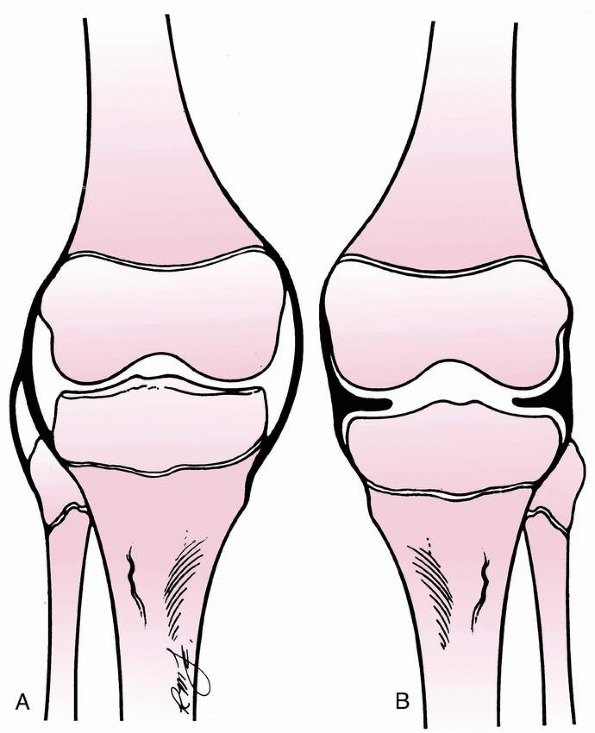

displaced tibial eminence fragment has been reported and may be a

rationale for considering arthroscopic or open reduction in displaced

tibial spine fractures (Fig. 24-5).54,59,94,177

Meniscal entrapment prevents anatomic reduction of the tibial spine

fragment, which may result in increased anterior laxity or a block to

extension.120,148,211,236,240 Furthermore, meniscal entrapment itself may cause knee pain after fracture healing.59 Falstie-Jensen and Sondergard Petersen,94 Burstein and colleagues,54 and Chandler and Miller59

have all reported cases of meniscal incarceration blocking reduction of

type 2 or 3 tibial spine fractures in children. The prevalence of

meniscal entrapment in tibial spine fractures may be common for

displaced fractures. As aforementioned, the anterior horn of the

lateral meniscus typically remains attached to the tibial eminence

fracture fragment. However, the anterior horn of the medial meniscus or

the intermeniscal ligament may become incarcerated. Mah and colleagues200

found medial meniscal entrapment preventing reduction in 8 of 10

children with type 3 fractures undergoing arthroscopic management. In a

consecutive series of 80 skeletally immature patients who underwent

surgical fixation of hinged or displaced tibial eminence fractures

which did not reduce in extension, Kocher et al.177

found entrapment of the anterior horn medial meniscus (n = 36),

intermeniscal ligament (n = 6), or anterior horn lateral meniscus (n =

1) in 26% (6/23) of hinged (type 2) fractures and 65% (37/57) of

displaced (type 3) fractures. The entrapped meniscus can typically be

extracted with an arthroscopic probe and retracted with a retaining

suture (Fig. 24-6).

FIGURE 24-5 Meniscal entrapment under a tibial eminence fracture.